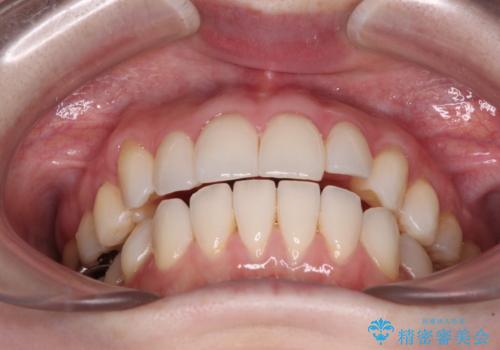

前歯のデコボコをインビザラインで改善

- 前歯のデコボコや八重歯の様になっていることを気にして来院された患者様です。

犬歯捻れて前方に飛び出しており、下顎前歯もそれに沿うようにデコボコとなっていました。

IPR(歯と歯の間を削る処置)によりスペースを獲得して上下顎前歯のデコボコを改善し、前歯が前方に突出しないように設定した上で、インビザラインにて矯正治療を行うこととしました。

途中体調を崩され、長い期間矯正治療を休むことになったため4年半ほどの治療期間がかかりました。